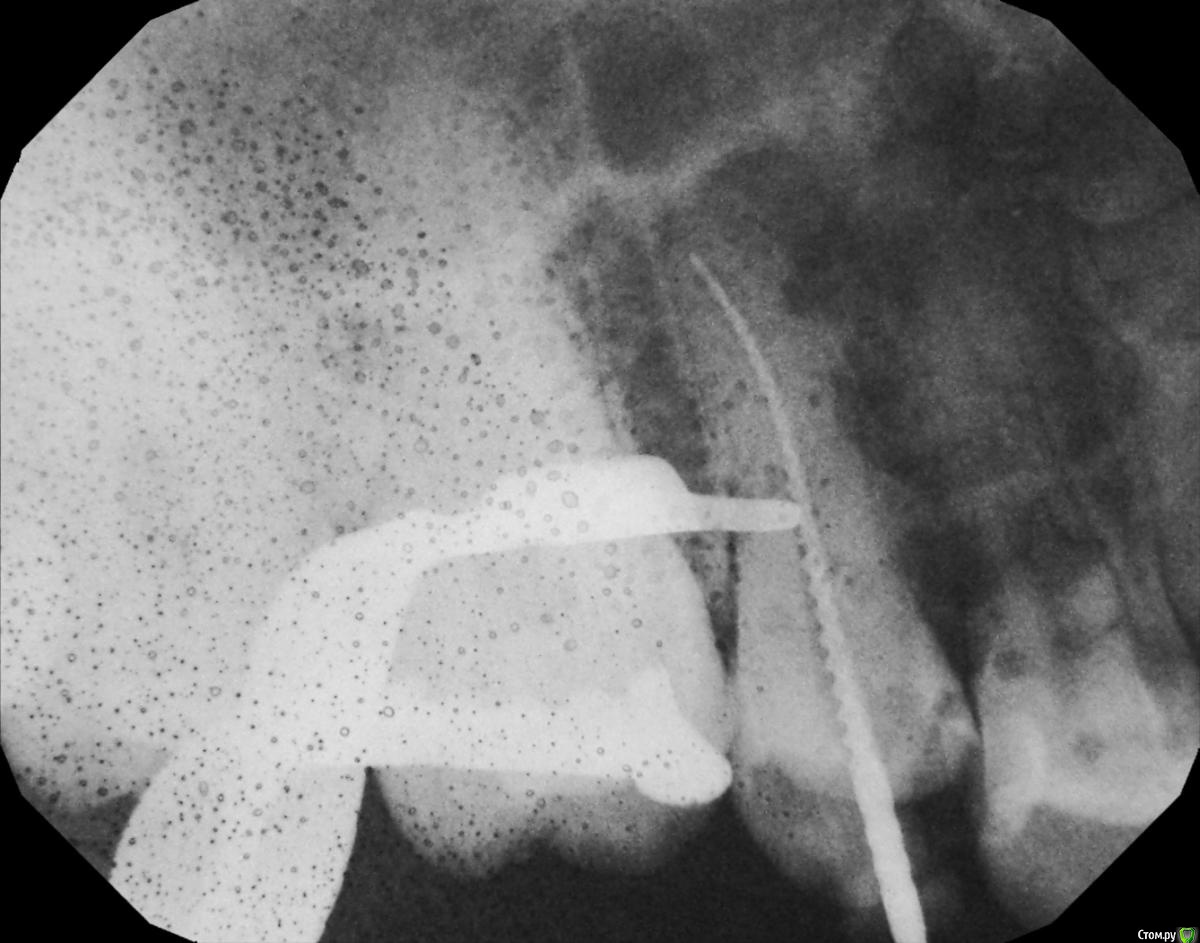

hichi Опубликовано 19 сентября, 2015 Поделиться Опубликовано 19 сентября, 2015 Добрый день. 6 месяцев назад проведено эндодонтическое лечение зуба. После этого через 1.5 - 2 недели острая боль от горячего. Подозревали дополнительный канал, зуб еще раз вскрыли, но ничего не обнаружили, еще раз обработали тот же самый канал и поставили кальций на 2 недели. На сегодняшний день реакции на горячее нет, но острая боль при чистке нитью между 1.4 и 1.5. когда вводишь и выводишь нить через контактный пункт. Как только пройдешь контактный пункт боль сразу же проходит. Десна не болит. Карманов нет. Кариеса тоже нет. Пару месяцев назад частично заменили пломбы в районе этого контактного пункта, но ничего не изменилось. Прилагаю снимок через 6 мес. Оцените, пожалуйста, все ли в порядке? Спасибо. Ссылка на комментарий

Гарриевич Опубликовано 21 сентября, 2015 Поделиться Опубликовано 21 сентября, 2015 кроме горячего и зубной нити на что то еще реагирует?в зубе сделан достаточно глубокий ложный ход, покажите все снимки начиная с первого Ссылка на комментарий

hichi Опубликовано 25 сентября, 2015 Автор Поделиться Опубликовано 25 сентября, 2015 (изменено) в зубе сделан достаточно глубокий ложный ход это "пробурили" когда искали дополнительный канал, после того как заболел от горячего. Док говорит что там нормально все перфорации нет. Изменено 25 сентября, 2015 пользователем hichi Ссылка на комментарий

hichi Опубликовано 25 сентября, 2015 Автор Поделиться Опубликовано 25 сентября, 2015 (изменено) покажите все снимки начиная с первого Гарриевич сказал(а) 22 Сен 2015 - 00:35: покажите все снимки начиная с первого + 1 пожалуйста первичное эндо когда заболел от горячего искали доп. анатомию кальций с ложным ходом есть только один снимок, который в самом первом сообщенииесть еще один через 3 мес после лечения но он не совсем удачно сделан, думаю ничем вам не поможет Изменено 25 сентября, 2015 пользователем hichi Ссылка на комментарий